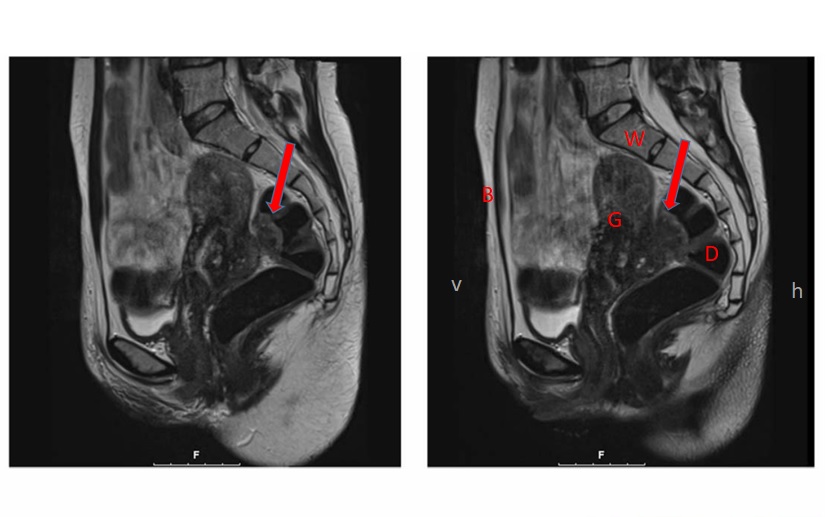

Endometriosis affects one in every ten women of childbearing age. It can cause severe pain, mainly during menstruation, and can be a factor for infertility. The disease is characterized by the growth of endometrium, the layer of tissue that normally covers only the inside of the uterus, outside of it. In rare cases, it can grow into other abdominal organs such as the bowel or the vagina (deep infiltrating endometriosis). This situation often requires surgery to remove endometriosis.

The study also shows that women with endometriosis had a slightly higher possibility of delivering smaller children (birth weight lower than average) and of suffering from elevated blood pressure during pregnancy. Moreover, a higher frequency of placenta previa was observed, a situation where the placenta blocks the birth canal.